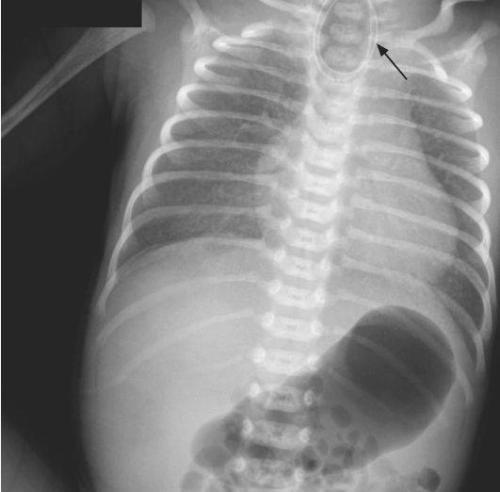

这可不是正常的现象 , 我们赶快把新生儿转入儿科治疗 。 转入后儿科给予了保暖、吸痰、留置胃管等处理 , 但在胃管留置中受阻 , 于口腔内迂曲 , 儿科主任潘医生再进行食管造影检查 , 检查医生发现小宝宝的食道没有连接到胃 , 到了中间居然中断了 。 潘医生判定 , 小婴儿得的是一种叫先天性食道闭锁的罕见病 。